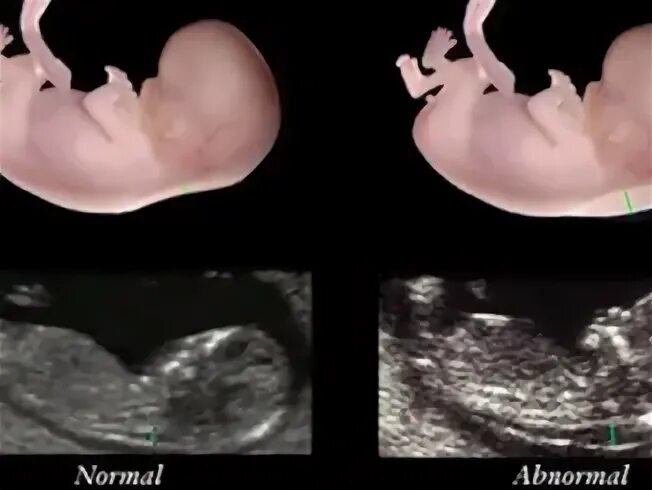

Воротниковое пространство 5